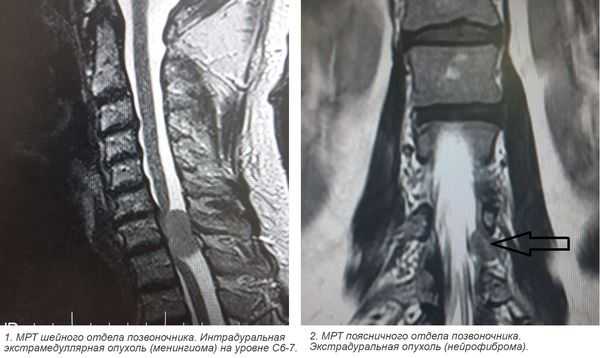

1. При подозрении на эпидуральную опухоль во всех случаях необходимо провести нейровизуализационное исследование, которое подтверждает диагноз эпидуральной опухоли и определяет ее верхние и нижние границы.

- Основным методом, применяемым для определения стадии заболевания и для планирования лечения, является МРТ. При невозможности проведения МРТ используют другие доступные и безопасные в конкретной сложившейся ситуации методы обследования.

3. Магнитно-резонансная томография (МРТ) с контрастным усилением. На данный момент это основной метод диагностики новообразований спинного мозга. МРТ позволяет визуализировать весь спинной мозг и позвоночник и определить локализацию опухоли. Накопление контрастного вещества определяет не только распространение, но и гистологическую структуру опухоли [5] [6] .

4. КТ-миелография. Применяют для выявления границ опухоли. Метод заключается в контрастировании субарахноидального пространства (полости со спинномозговой жидкостью между мягкой и паутинной оболочками спинного мозга) водорастворимыми веществами. В комбинации с МРТ или КТ позволяет значительно улучшить диагностику опухолей спинного мозга, особенно в окружающих его тканях.